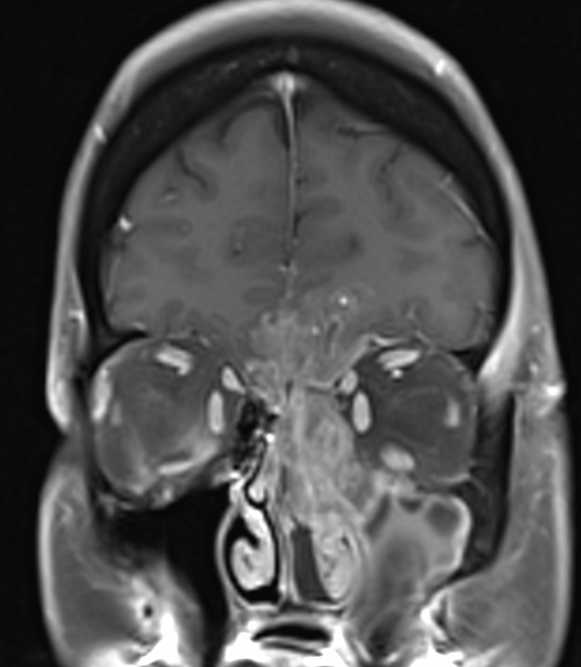

Dona de 59 anys, fumadora de 15-20 cigarretes/dia fins fa 10 anys, sense altres hàbits tòxics destacables, amb antecedents patològics de Diabetes Mellitus tipus I que tracta amb insulina, Hipertensió arterial, i dislipèmia. Consulta per cuadre progressiu desde fa 5-6 mesos d'anosmia, cefalees hemicraneals esquerres, hipoestesia d'hemicara esquerra, epistaxis esquerres que es fan diàries, visió borrosa amb diplòpia, i tumefacció cervical esquerra. A l'exploració física s'observa exoftalmos esquerre i adenopaties laterocervicals esquerres indurades, i a l'estudi ORL s'observa lesió polipoidea eritematosa a fossa nasal provinent de meat superior esquerre. Es realitzen diverses proves de Diagnòstic per la imatge, i es realitzen simultàniament punció aspirativa i biòpsia de la lesió a fossa nasal. S'adjunten imatges de la RNM cranial, i de punció aspirativa.